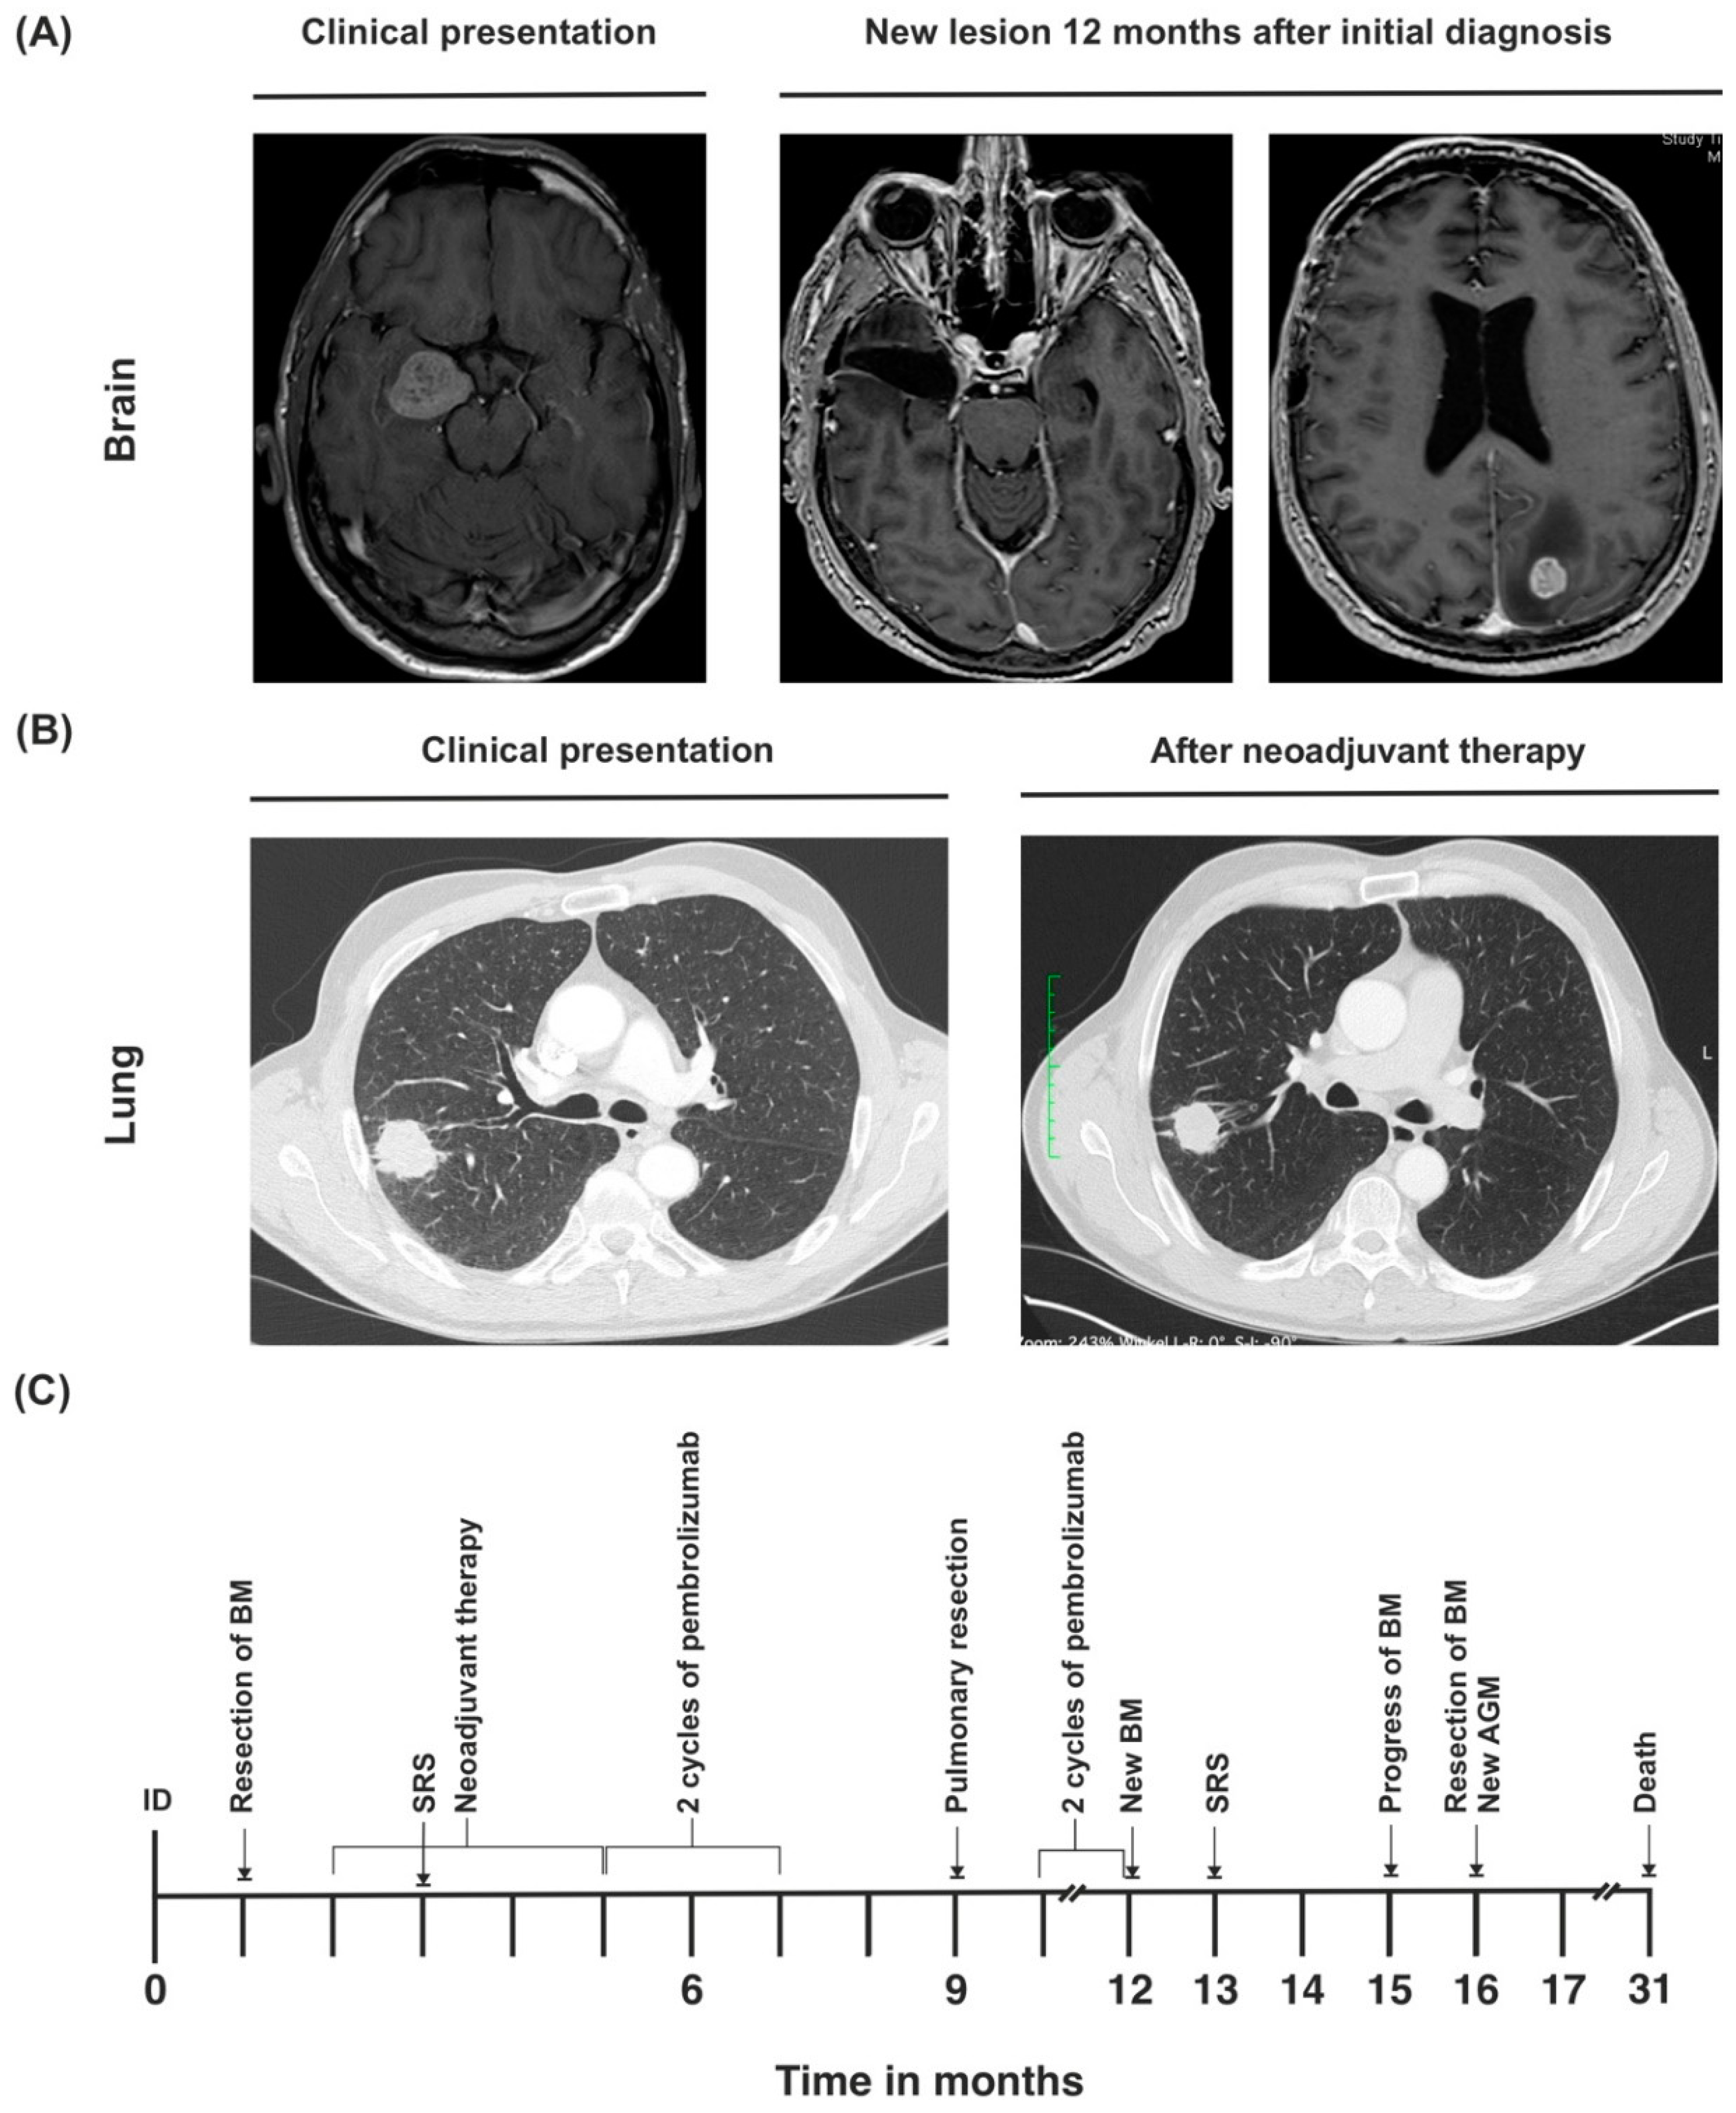

3.2. Case 2

| Treatment of BM | Neurosurgery and SRS | Neurosurgery and SRS | SRS |

| BM radiation dose | 21 Gy | Synchronous BM: 21 Gy, metachronous BM: 20 Gy | 19 Gy |

| Neoadjuvant therapy | Cisplatin (75 mg/m2), pemetrexed (500 mg/m2), and pembrolizumab (200 mg) | Cisplatin (75 mg/m2), pemetrexed (500 mg/m2), and pembrolizumab (200 mg) (+2 cycles of pembrolizumab as maintenance therapy) | Cisplatin (75 mg/m2), pemetrexed (500 mg/m2), and pembrolizumab (200 mg) |

| Pulmonary resection | Posterolateral thoracotomy, subsegment S1-resection, right lower lobe resection, systematic lymph node dissection | Posterolateral thoracotomy, extrapleural extended upper lobectomy, wedge resections (S1, S5, S6), systematic lymph node dissection | Posterolateral thoracotomy, extended left lower lobe resection, wedge resection S1, systematic lymph node dissection |

| Tumor stage after lung resection | ypT0 ypN0 (0/42), L0, V0, R0, Gx, pM1b (BRA), UICC IVA | ypT2b ypN0 (0/22), L0, V0, Pn0, R0, Gx, pM1b (BRA), UICC IVA | ypT2a ypN3 (5/23), L1, V1, Pn0, R0, cM1c (BRA), UICC IVB |

| Maintenance therapy | 200 mg per cycle (ongoing) | 200 mg per cycle (discontinued after 2 cycles because of progressive disease) | 200 mg per cycle (finished after 24 months) |

| Current Karnofsky performance index | 100% | 0% | 100% |